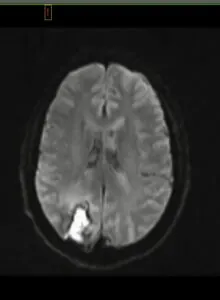

The swift response of emergency services led to stroke protocols and a subsequent CAT scan, which unveiled something unexpected: a mass in the back of his brain. A biopsy followed the next day, along with high doses of steroids to combat the swelling. Eric believes he started taking prednisone that very day, or within a couple of days. After a week of recovery at Northwestern Central DuPage Hospital, Eric was sent home with an unspoken diagnosis of brain cancer.

However, the respite was short-lived. “I was home for a day and a half when the neurologist called, on a Sunday, instructing me to return to the hospital as soon as possible and go to the ER,” Eric explained. The news was significant: It wasn’t cancer, but central nervous system (CNS) vasculitis. Eric’s brain biopsy and bloodwork were tested for everything imaginable, including cancer, infectious diseases, and even fungus. It was the lab’s inability to culture anything from the biopsy along with certain markers in his bloodwork that led to the CNS vasculitis diagnosis.

This time, at Northwestern Hospital in McHenry, Eric’s condition escalated. “I became psychotic, with true hallucinations and altered reality.” The ICU neurology team, including nurses trained in the care of neurology patients, intensified steroid treatment, but instead of improvement, Eric’s condition worsened. Days of EEGs revealed a concerning pattern: near-constant mini-strokes and seizure activity. The ICU doctor was a neurologist who shifted the medical team’s approach, introduced a variety of anti-seizure medications and intravenous immunoglobulin (IVIG). Gradually, Eric’s brain began to calm down. “It was a very long 16 days before I was discharged on three anti-seizure medications,” he noted.

Now, months later, there’s a glimmer of hope and evidence of Eric’s resilience. At the time of this interview, Eric had recently finished seven months of chemotherapy, and the MRI conducted shortly afterward showed no new abnormalities, confirming the treatment’s effectiveness. “EEG didn’t show any signs of seizure or stroke activity in the brain. Next step is to taper off prednisone (hopefully).”